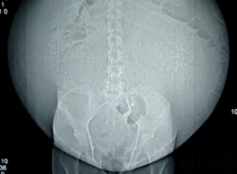

Extirpan tumor de 36 kilos a loretana

Médicos del Instituto Nacional de Enfermedades Neoplásicas (INEN) extrajeron un tumor de 26 kilos a Amelita Guevara (26), quien muestra buena recuperación.

El gigantesco tumor tenía 80 centímetros de diámetro y por su peso y dimensiones desde hacía meses impedía a la paciente movilizarse, por ello permanecía en cama en Loreto, su tierra natal.

La operación duró tres horas, según informó Eduardo Payet Meza, médico a cargo de la intervención quirúrgica.